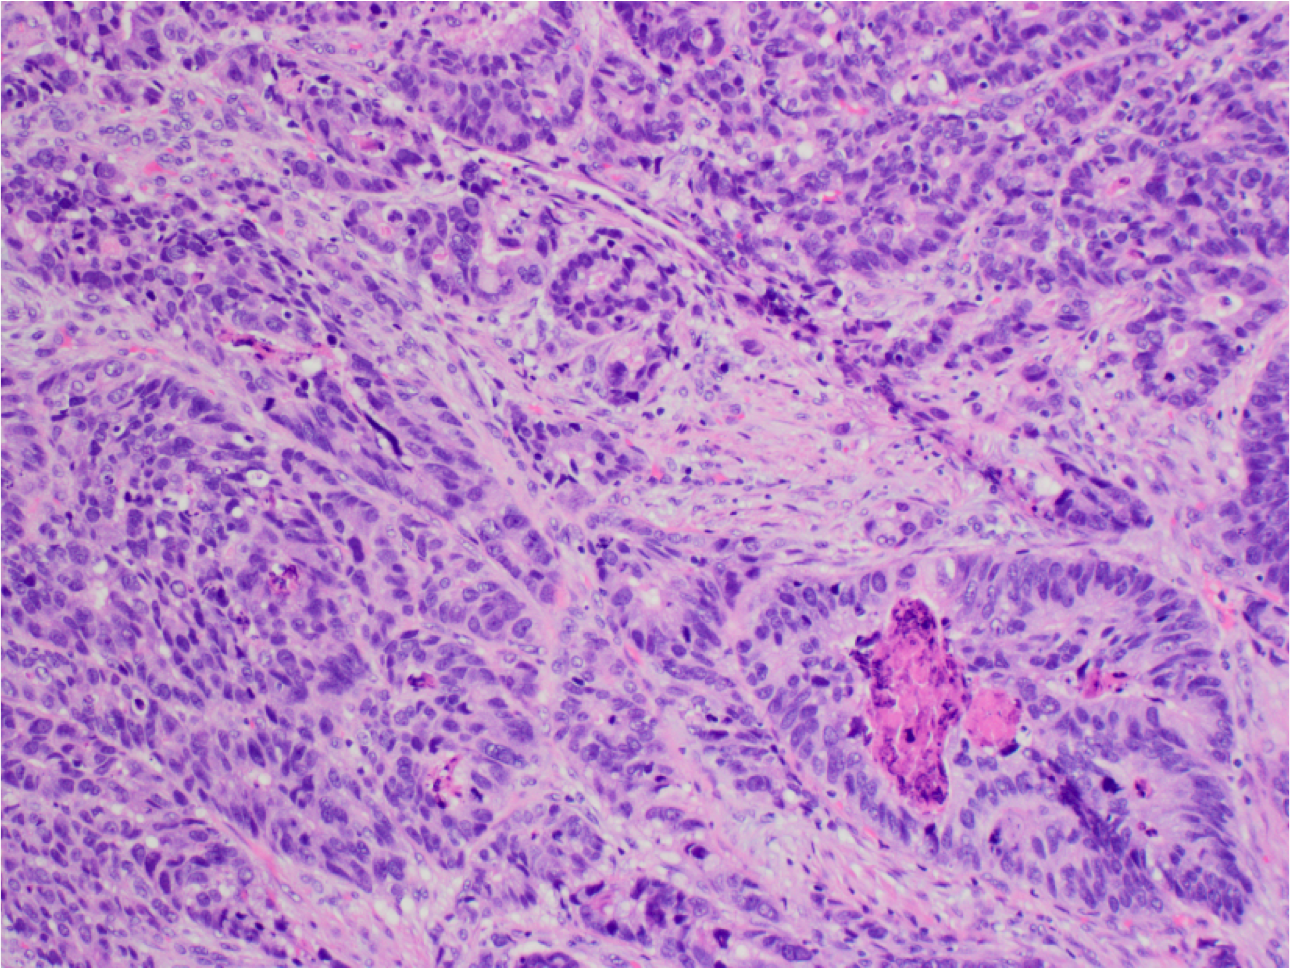

What’s this?

Gastric Adenocarcinoma.

High power view of malignant glands. Note irregular shape and complexity of the glands with abortive lumina, necrotic debri, nuclear enlargement and mild nuclear pleiomorphism